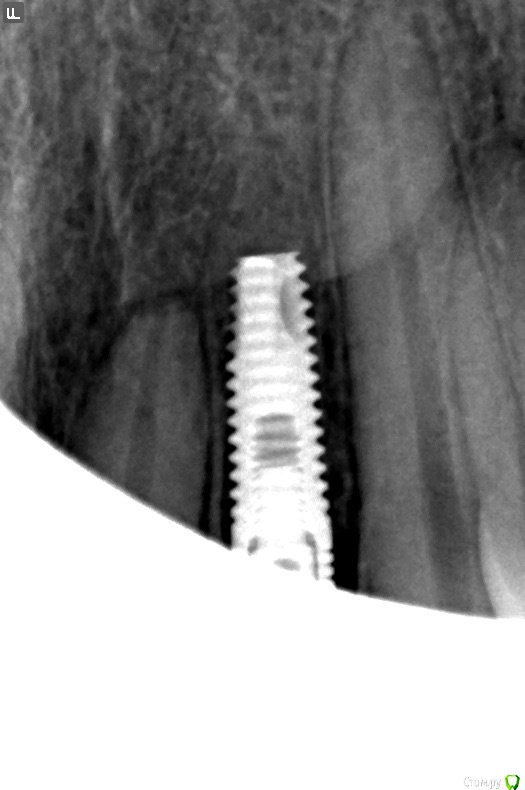

20 дней назад провели операцию по установке имплантата (альфа био). Операция длилась минут 30-40, по ощущениям прошла хорошо, самочувствие было удовлетворительное. Вчера обнаружил шишку над местом, куда поставлен имплантат. Сегодня приехал в клинику, до вскрытия этой шишки врач сказала, что это "скорее всего мембрана и она ее удалит", вскрыла, минут 30 были какие-то манипуляции. По окончанию узнал, что имплантат удалили. Врач сказала, что после разреза увидела, что кость на передней стенке наполовину рассосалась, поэтому и удалила.

Прилагаю снимок, сделанный сразу после операции и полное название установленного имплантата (если это важно).